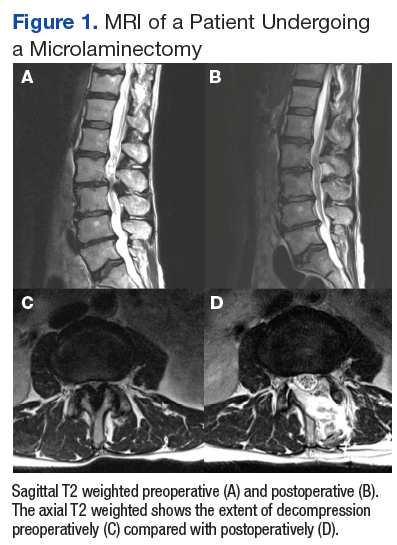

Fifty veterans with severe lumbar stenosis and neurogenic claudication underwent a 1- or 2-level laminectomy at SAVAHCS (Table). A traditional laminectomy was performed for all patients until conversion to the MIS procedure, then all subsequent patients underwent the microlaminectomy. There was 1 female patient in each group. The preoperative magnetic resonance imaging (MRI) of the patients showed severe spinal canal stenosis defined radiographically by the absence of cerebrospinal fluid signal at the affected level on MRI (Figures 1A and 2A) and clinically by the presence of neurogenic claudication.

The open laminectomies were performed in a traditional midline approach with removal of the spinous process along with the lamina bilaterally to provide spinal canal decompression (Figure 2).

The MISS laminectomies were performed through a small unilateral paramedian incision created 1.5 cm from the midline.1 A tubular retractor system was used, and the laminectomy was performed under microscope magnification. A laminotomy initially was completed ipsilateral to the side of the incision until the ligamentum flavum and the lateral recess of the spinal canal were identified. The tube was then aimed medially so that the base of the spinous process was identified and resected. The ligamentum flavum was dissected from the undersurface of the contralateral lamina. The contralateral lamina then was resected using a high-speed drill. Finally, the ligamentum flavum was resected, and the dura was exposed. The cranial-caudal extent of the resection was confirmed using fluoroscopy. The technique allowed for significant canal expansion (Figures 1A, B, C, and D).